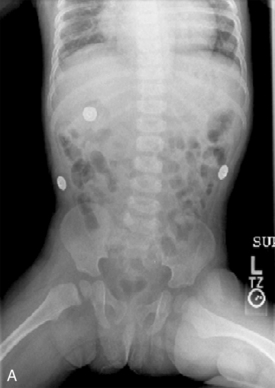

64 Yazigi N.A., Balistreri W.F. Acute and chronic viral hepatitis. In Suchy F.J., Sokol R.J., Balistreri W.F., editors: Liver disease in children, ed 2, Philadelphia: Lippincott Williams and Wilkins, 2001.